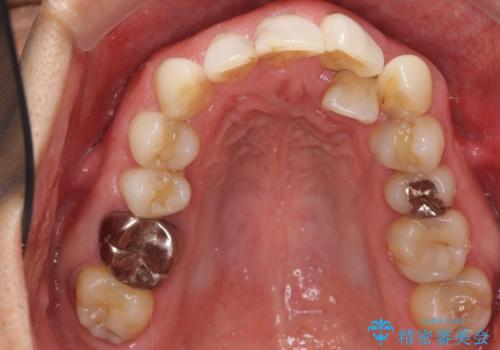

矯正治療とホワイトニングを提案しましたが希望されず、「接客関係の仕事で矯正治療は考えられない、短期間で治療を終わらせたい、ホワイトニングでは難しい位の人工的な白さにしたい」とのご要望により、治療前にワックスアップ模型を作製し何度もコンサルテーションを重ね、治療方針を決定しました。

歯頚ラインが変えられないことや天然歯を削るリスクをご理解頂いた上で、オールセラミッククラウンによる補綴治療を行いました。(見えない奥歯のみ天然歯のままとしました)

下の前歯1本だけ歯軸を変えるために神経をとり根管治療を行っております。

それ以外の歯は神経をとらずに済むよう、慎重かつ丁寧に歯の形態を整えました。

治療前に埋伏している親知らずの抜歯をおすすめしましたが、ご希望されませんでした。